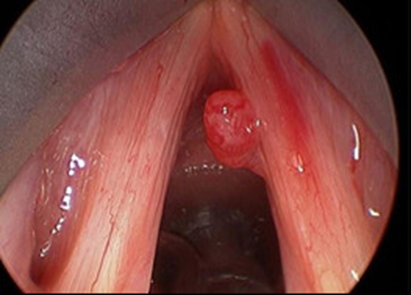

Hình 4 :U nang dây thanh

1.3.  U nang dây thanh:

• Bề mặt của dây thanh quản được phủ bởi biểu mô có tuyến nhầy và được sắp xếp tạo ra các nếp gấp. Chính các nếp gấp này khiến cho dây thanh dễ rung hơn và tạo thành giọng nói. Âm sắc của tiếng nói, tiếng hát khác nhau giữa từng người là phụ thuộc vào sự đa dạng của các cấu trúc này. Vì có kết cấu là các nếp gấp, đôi khi một trong những tuyến tiết nhầy trên lớp biểu mô này sẽ không thoát được dịch tiết ra ngoài. Hệ quả là sự tích tụ chất nhầy có vỏ bọc sẽ tạo thành u nang dây thanh.

Nguyên nhân:

U nang dây thanh có thể xảy ra thứ phát do lạm dụng giọng nói quá nhiều hoặc có thể là do lớp biểu mô bị mắc kẹt trong các nếp gấp. Bên cạnh đó, các u nang tích trữ chất nhầy có thể xảy ra tự phát hoặc có thể liên quan đến việc vệ sinh giọng nói kém. Khi sự tích tụ ngày càng nhiều, kích thước u nang tăng lên, chúng có thể bắt đầu gây ảnh hưởng đáng kể đến vùng rung của dây thanh âm và biểu hiện qua sự thay đổi giọng nói.